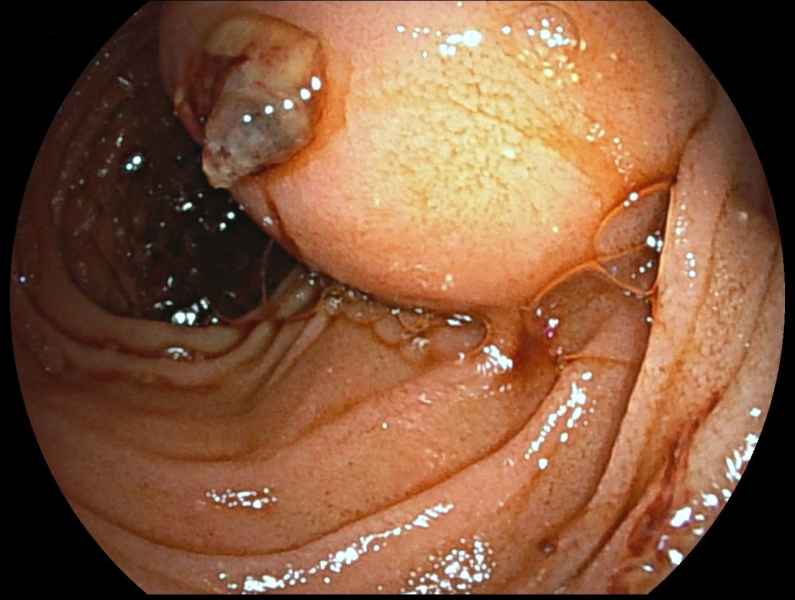

Hybrid endoscopic full-thickness resection of an appendicular laterally spreading tumour

Fotografia